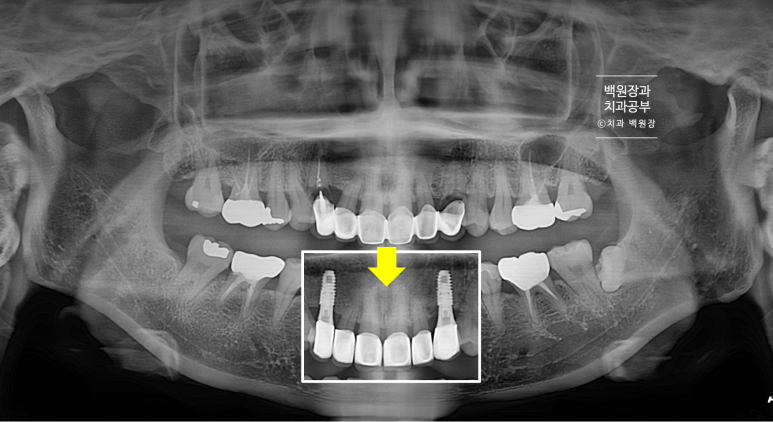

노란색 화살표로 가리킨 곳에 파노라마 엑스레이상 소견으로 까맣게 충치가 생겨있는 것을 볼 수 있죠.

치료 완료 후 치과용 파노라마 엑스레이 사진입니다!

아주 깔끔하게 6개의 크라운이 잘 제작되어 있는 것을 보실 수 있을거에요.

치료 전 후를 비교해보면, 여섯개의 크라운이 따로 제작되어 모두 떨어져 있는 형태를 가지고 있고 두개의 임플란트는 아주 가지런한 방향으로 잘 수술되어 있는 것을 보실 수 있을겁니다.